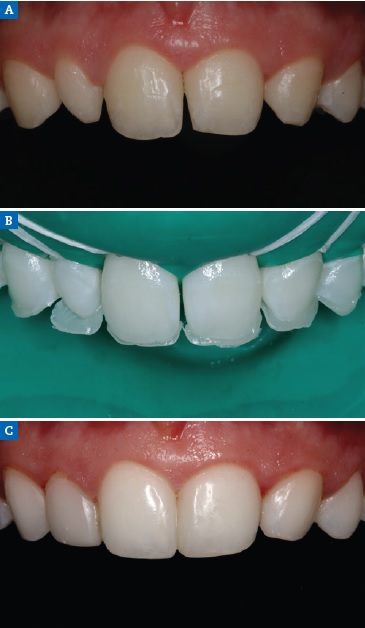

Left maxillary canine contouring procedures (Figures 8 and 9) were performed as indicated by the diagnostic wax-up.19 First, the canine eminence was reduced on the labial surface, and the tip of the canine was flattened to produce an incisal edge. Second, the distal incisal angle was slightly rounded to reproduce a lateral incisor. Third, ORMOCER® (ORganically-MOdified-CERamic) composite (Admira Fusion, VOCO, Cuxhaven, Germany) without bisphenol A (BPA) was added to the adjacent teeth to improve the distal and mesial dimensions of the left maxillary central incisor and left maxillary first premolar, thereby diminishing the canine and harmonizing the smile line (Figure 14). In addition, because the mandibular primary left central incisor presented mobility due to root resorption, it was extracted, and the mandibular primary right central incisor was restored (Figure 15).

Figure 14 Case 2 restorative protocol: (A) Preoperative view, (B) Palatal shell in composite based on silicone matrix obtained from the wax-up, (C) One-year recall.